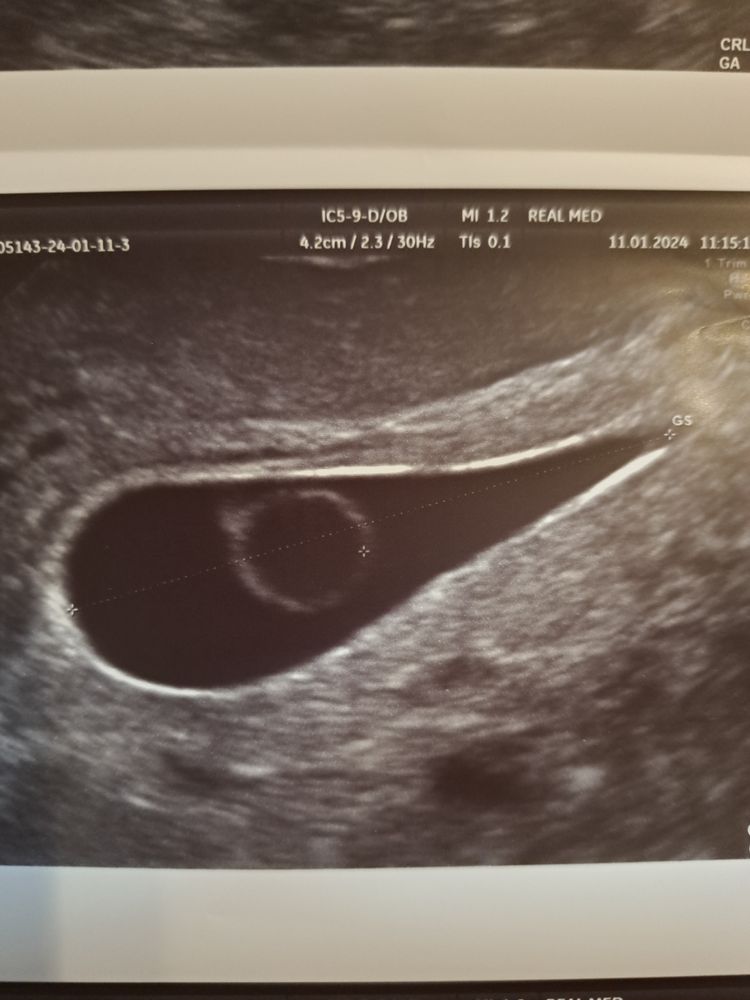

Пошла на узи. Эмбриончик на 5 недель, по месячным 7 недель 4 дня, сердцебиение отсутствует. Огромный желточный мешочек. Грусть, печаль😭

Эмбрион на 5 нед 5 дней

Желточный мешочек 7.8 мм больше нормы этого срока в 2 раза

Плодное яйцо на 8 недель по размерам